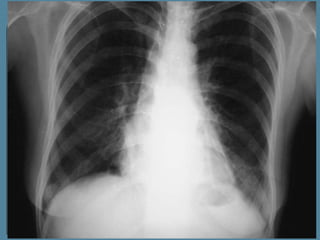

 La

TAC torácica y de

abdomen superior

mostró una atelectasia

segmentaria en

segmento B6 derecho,

sin objetivar lesiones

hiliares o

parenquimatosas

pulmonares ni

adenopatías

patológicas hiliares ni

mediastínicas